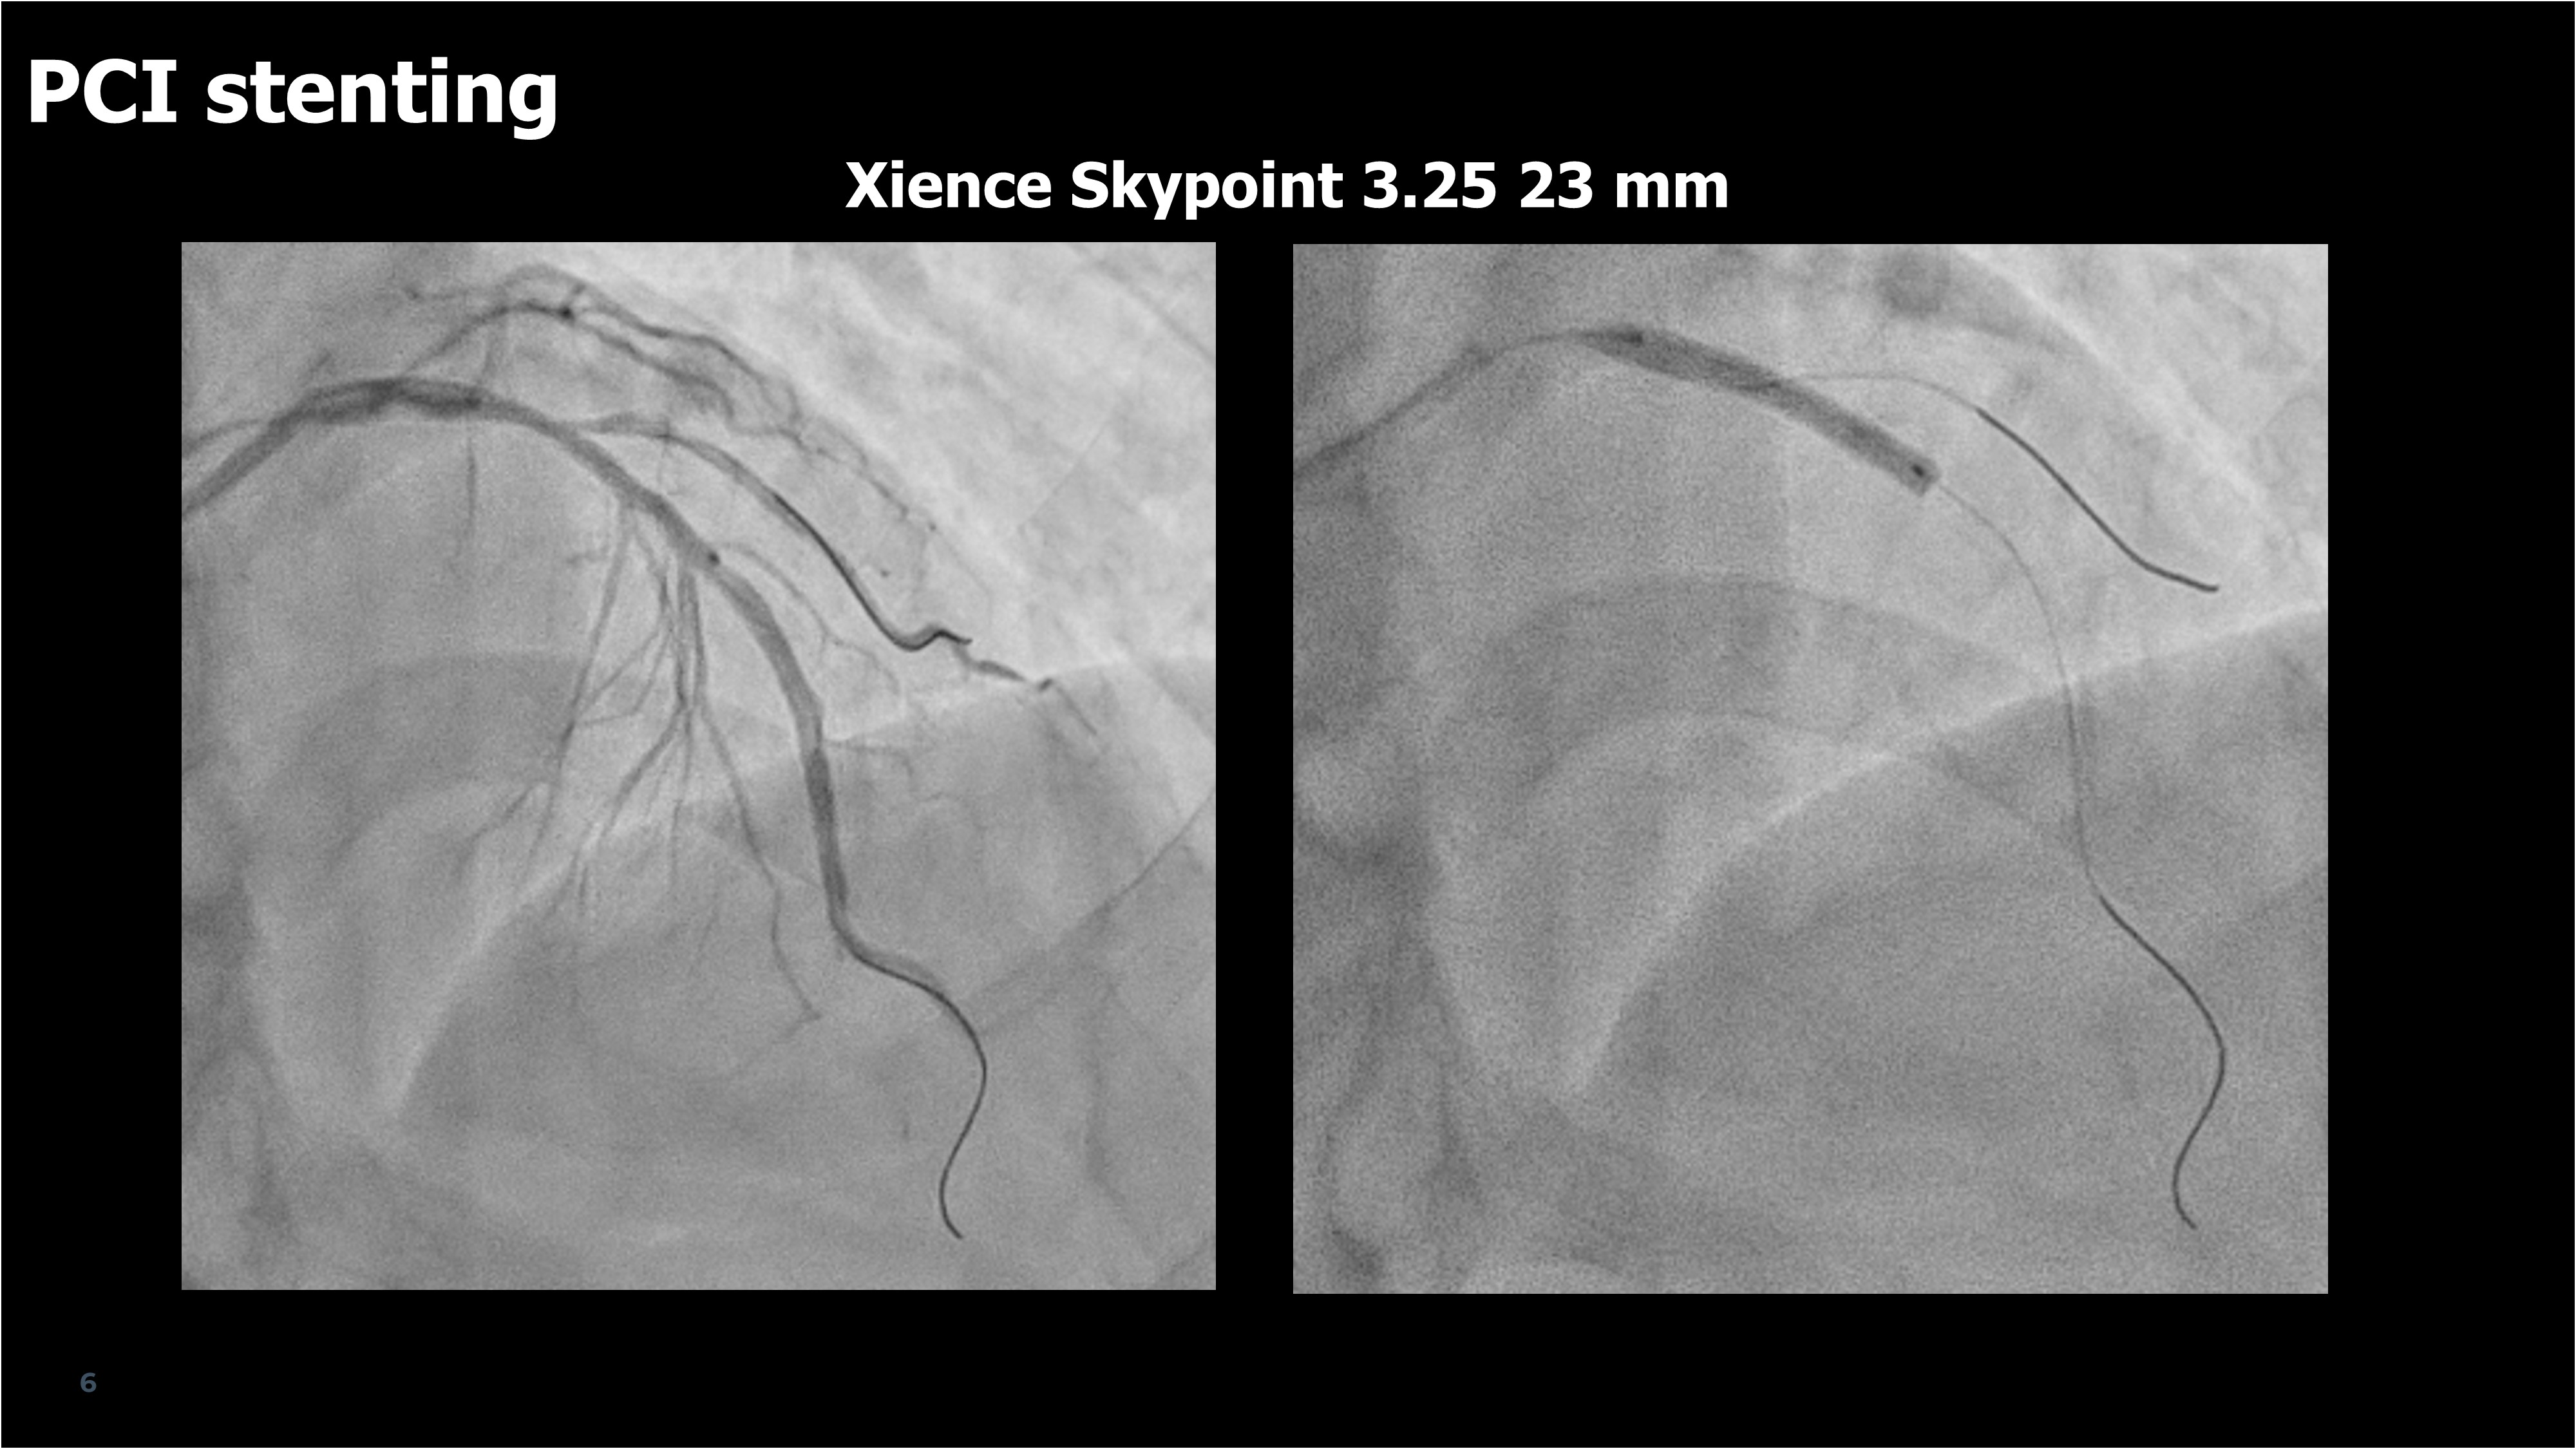

Following the CT-guided plan, PCI was performed without intravascular imaging, in accordance with the P4 study protocol.A 3.0 ¡¿ 23 mm drug-eluting stent (Xience Skypoint, Abbott Vascular, USA) was deployed in the proximal LAD, with wire protection for the diagonal branch supplying 14% of myocardial mass. Post-dilatation achieved optimal expansion confirmed by stent enhancement. The final angiogram showed excellent result with preserved side branch flow.Invasive FFR improved from 0.67 to 0.94, closely matching the predicted FFRCT value (0.92). The procedure was uneventful, and no complications occurred during 30-day follow-up.